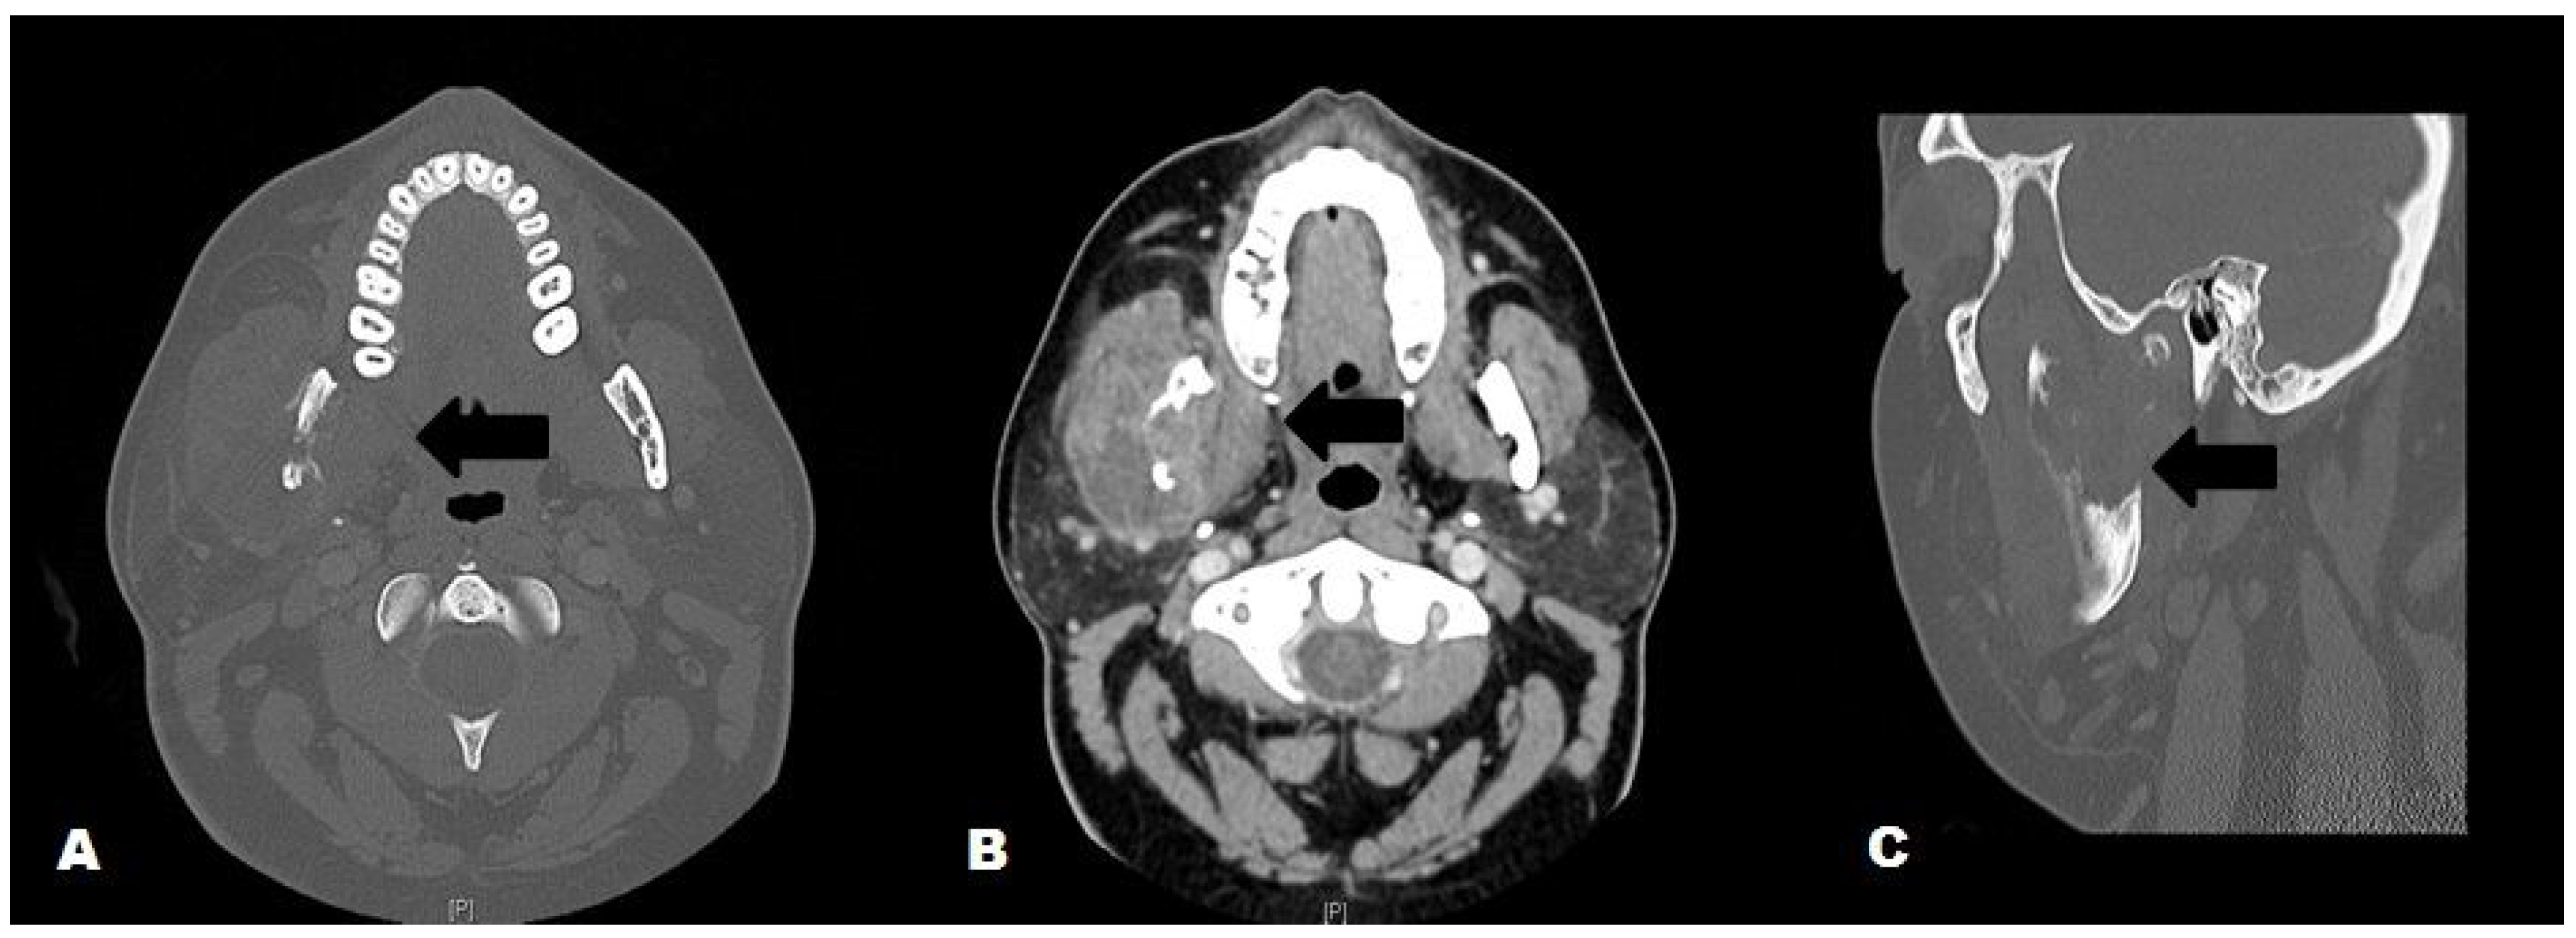

Figure 1.

Maxillofacial CT with contrast; A. Axial view, bone window: Enlarged right masseter and lytic destruction of the right mandibular ramus (black arrow); B. Axial view, soft tissue window: Enlarged right masseter with loculated abscess, adjacent lytic destruction of the mandibular ramus (black arrow); C. Sagittal view, bone window: Lytic destruction of the right mandibular ramus (black arrow).